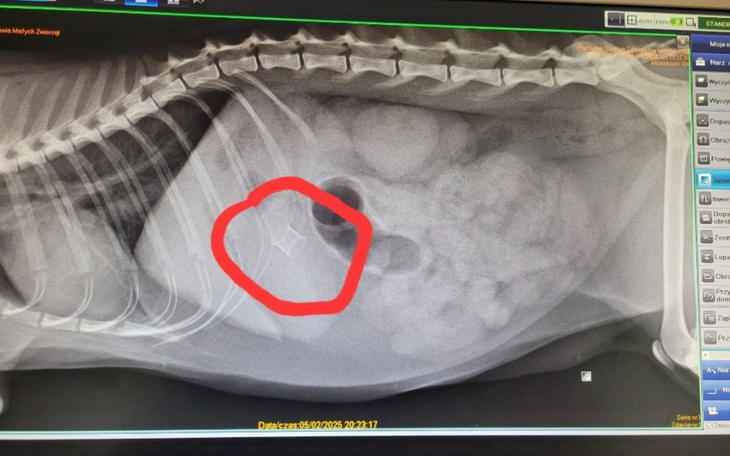

Jednak Rudi zaskoczył nas wszystkich, przestał jeść, przestał wydalac. Po prześwietleniu okazało się, że w jego żołądku znajduje się ciało obce. Nie było czasu na namysły trzeba było działać.

Operacja chirurgiczna aby usunąć ciało obce, Rudi został w szpitalu, następnego dnia kosztowna operacja, która uratowała jego życie. Gdyby nie to, że został złapany na działce możliwe że odszedłby tam 💔💔😪😪

Dziś został wypisany. Właśnie trafil do domu tymczasowego. Jutro mamy kontrolę a za 10 dnj zdjęcie szwów. Pewnie jesteście ciekawi to ciało obce to ptasia obrączka:/ nigdy w historii naszej fundacji nie trafił się nam taki pacjent.